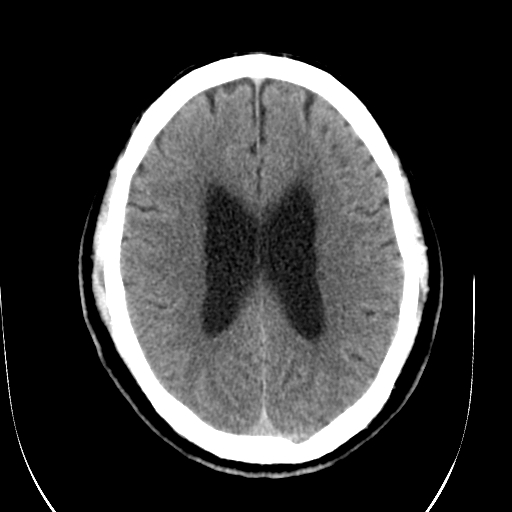

标题: CT28335:男,58岁,请各位看看是不是有脑积水,蝶窦内高密 [打印本页]

标题: CT28335:男,58岁,请各位看看是不是有脑积水,蝶窦内高密

轻度积水,蝶窦正常。

脑积水!建议行mri!

1)脑积水。2)副鼻窦炎。